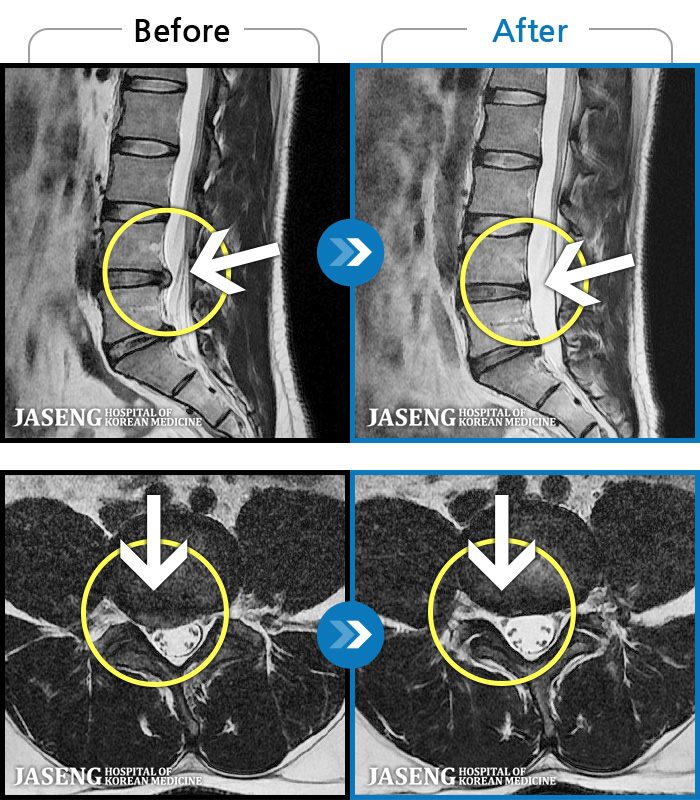

MRI ũ ʸ Ȯϼ.